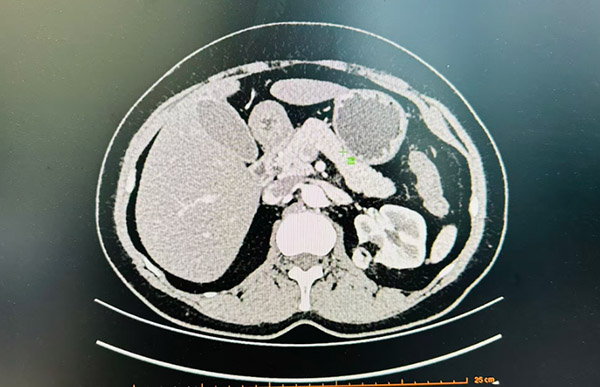

CT影像

话说回来,她的就诊过程还是蛮曲折的。之前在我们科门诊查出来肾错构瘤的时候体积并不大,可是随着定期复查逐渐发现:错构瘤有着明显增大的趋势,近期检查已超过4cm。她对于逐渐增大的肿物陷入到了自我内耗之中,一方面不断地CT检查已经让她心理上有所抗拒,另一方面错构瘤体积的不断增大亦使她陷入到了层层担忧之中:错构瘤继续增大,会不会有一天出血破裂?会不会有一天变成恶性?如果手术会不会对肾脏影响很大?

可是,如果将肾动脉完全阻断,会造成肾脏一过性供血不足,对于肾脏本身也会造成缺血性损害和缺血后再灌注损伤,长时间阻断(超过30分钟)后部分患者术后甚至可能会出现肾萎缩。经过仔细研读患者影像资料,考虑再三,蔡主任决定选择一项损伤最小的方法:高选择性阻断肾动脉供应错构瘤部位的动脉分支,这样的话既可以把对患者肾脏缺血性损害降至最低(肿瘤区域以外的肾脏供血不受影响),也可以使术中切除肿瘤时出血的可能性降到最低。